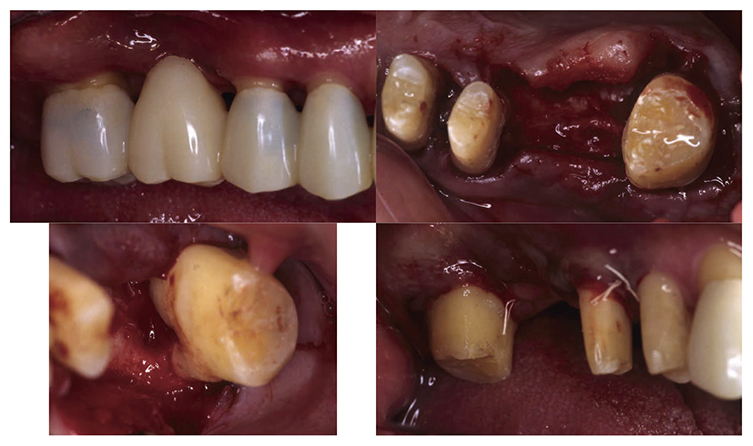

6) Prosthetic treatment

After orthodontic treatment was completed, fabrication of the final prosthesis was started.. Preliminary impression of the maxilla and mandible were taken, anatomic facebow and checkbite were obtained, and prosthetic diagnosis was performed. In the treatment plan before surgery, the first choice for the maxilla was the full mouth bridge that connects all teeth. However, since no parallelism was seen on the anchor teeth, and additionally all teeth were vital teeth, convenient pulpectomy was sought as a possibility. Additionally, in designing treatment for patients with severe periodontitis, to disperse the occlusal load to the entire jaw, which was most important, semi-fixed multi-tooth prosthetic using key and keyway attachment was designed for final prosthetic in this case. After taking parallelism of anchor teeth into consideration, multi-tooth models with attachments were designed for 13 and 14, and for 22 and 23. After deciding on the shape of prosthetics, anchor teeth were formed, impression was taken, and subsequently final confirmation was made on accurate fit with coping trial. After final prosthetic treatment on the maxilla, prosthetics were placed on the mandible starting with 47. Since metal crowns were placed on both 47 and 36, onlay-type metal crowns were placed on 44, 45, 34 and 35 for occlusal support. After completion of prosthetic treatment on all teeth, confirmation was made with an occlusal force tester (Dental Prescale®,GC, Tokyo) that occlusal force was equally distributed across the entire jaw. Additionally, nighttime bruxism was addressed by producing and applying nightguards since the patient had the habit of clenching.

7) Reevaluation testing (December 2003)

At the reevaluation examination after treatment to restore oral function, the color of gingiva was pink, and with prosthetics, intraoral harmony was replicated esthetically and functionally. (Fig.6a). The average PD across the entire jaw was 2.1mm, maximum PD was 4.0mm, the ratio of PD of 3mm or below was 99.3%, no BOP was found and the condition of the periodontal tissue was stable (Fig.6b). In the X-ray, continuity of the alveolar hard line was replicated and the sequence of bone trabeculae was normal, and therefore, the patient transitioned to the SPT phase (Fig.6c).

Fig 6a

(Fig.6a) Intraoral photo after completion of restoration of oral function was completed(2013.4)

Fig 6b

(Fig.6b) Reevaluation and examination after completion of restoration of oral function (April 2013)

Fig 6c

(Fig.6c) Digital X-ray 14 after completion of restoration of oral function (April 2013)